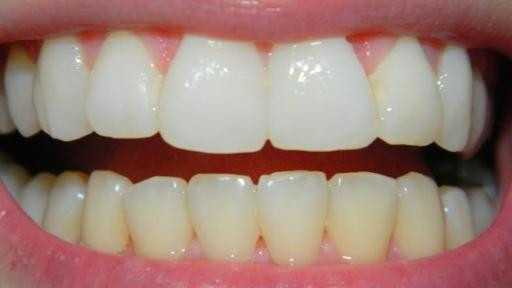

На странице представлено портфолио стоматологий Москвы с фото работ до и после исправления прикуса брекетами. Мы публикуем результаты разных клинических случаев: от скученности зубов и диастем до сложных ортодонтических аномалий. В каждом случае показан реальный прогресс — от начального состояния зубов до финального результата после снятия брекетов и исправления прикуса. Поэтому вы можете наглядно увидеть, как меняется положение зубов и общая эстетика улыбки. Изучите результаты работ до после и выберите подходящую клинику в Москве.